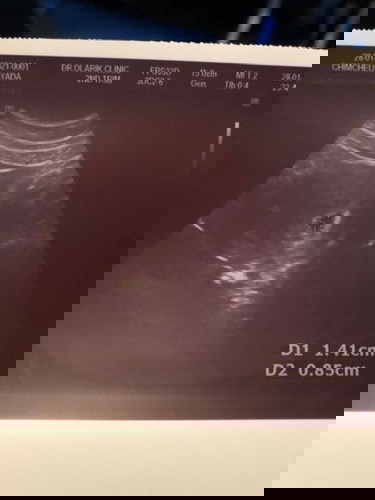

สอบถามแม่ๆหน่อยจ้า .. ท้อง2 ท้อง 5w5d ตอนบ่ายไปซาวด์มาเจอแต่ถุงตั้งครรภ์ แม่ๆว่าผิดปกติไหมคะ ปล.ท้องแรกท้องลมจ้า ตอนนี้เครียดมาก ฝากแม่ๆคอมเม้นต์หน่อยจ้า 😰😰

ไปซาวด์เมื่ออาทิตย์ที่แล้ว 5w5d เหมือนกัน เห็นแต่ถุงเหมือนกันค่ะ อีก 20 วัน หมอนัดซาวด์อีกครั้งค่ะ ลุ้นไปด้วยกันค่ะ